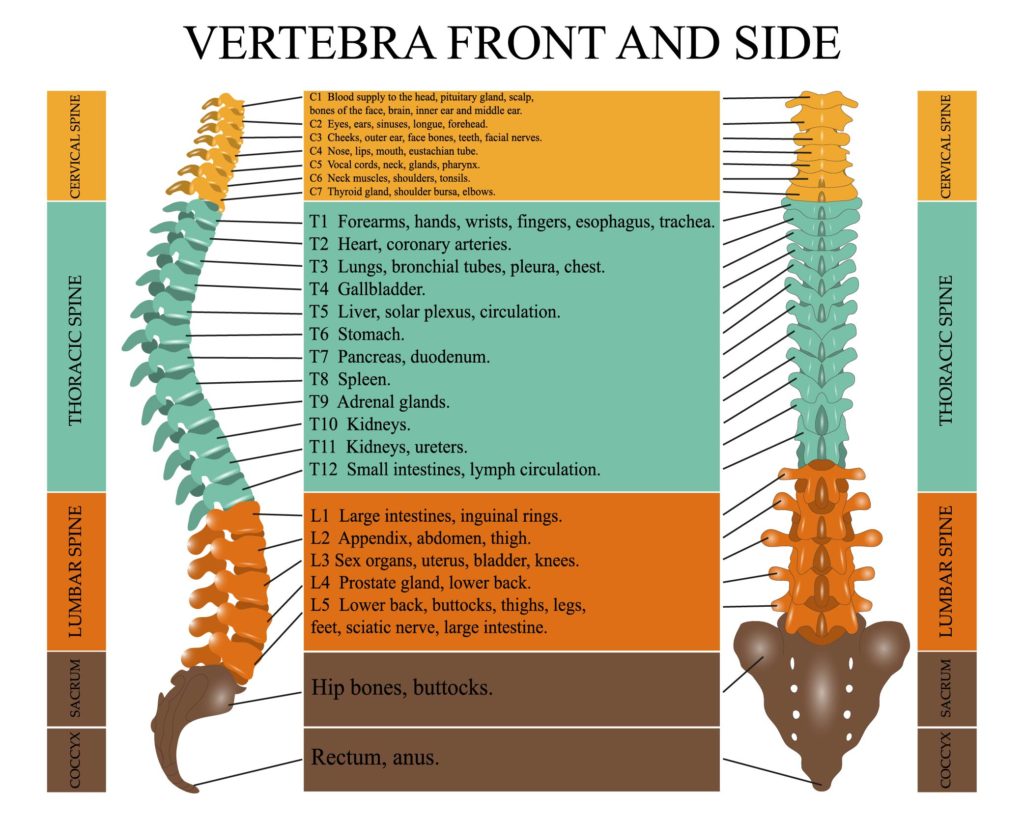

The illustration provided is an anatomical diagram showing the vertebral column from both the front (anterior) and side (lateral) views. It specifically highlights the different regions of the spine: cervical, thoracic, lumbar, sacral, and coccygeal. Each region is color-coded and labeled with the corresponding vertebrae from C1 to the coccyx. Alongside the vertebrae, there are annotations that link each spinal segment to various organs and body parts, indicating the areas potentially affected by the nerves that emanate from that segment of the spinal cord.

The cervical spine is at the top of the diagram, consisting of 7 vertebrae (C1-C7), associated with the head, neck, diaphragm, thyroid gland, and shoulders. This region of the spine is flexible, allowing for a wide range of head and neck movements.

The thoracic spine is below the cervical region and consists of 12 vertebrae (T1-T12). This region is more rigid, providing stability and supporting the rib cage. The nerves from these vertebrae are associated with many internal organs, such as the heart, lungs, gallbladder, and kidneys.

The lumbar spine follows with 5 vertebrae (L1-L5), associated with the lower back. This region bears the most weight and is thus more prone to injury. The nerves from the lumbar region innervate the lower abdominal muscles, hips, and legs.

Next is the sacral region, which is represented by a triangular bone made up of fused vertebrae, followed by the coccygeal region at the very bottom, often referred to as the tailbone.

The diagram also indicates the different curves in the spine: the cervical and lumbar regions have a lordotic curve, which means they curve inward toward the body, while the thoracic and sacral regions have a kyphotic curve, curving outward.

Such a diagram is useful in understanding the relationship between spinal health and overall well-being, as spinal problems can affect various organs and limbs due to the complex nature of nerve innervation.